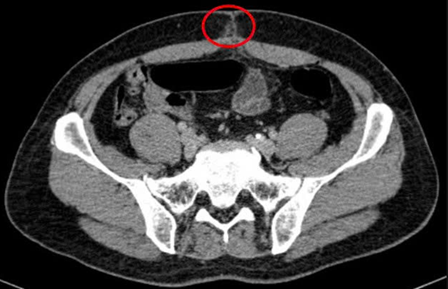

– Chụp cắt lớp vi tính ổ bụng (06/08/2025) – sau phẫu thuật:

Hình 2: Hình ảnh chụp cắt lớp vi tính ổ bụng: Hình ảnh thâm nhiễm mỡ vùng hạ vị quanh vị trí vết mổ (vòng tròn đỏ).